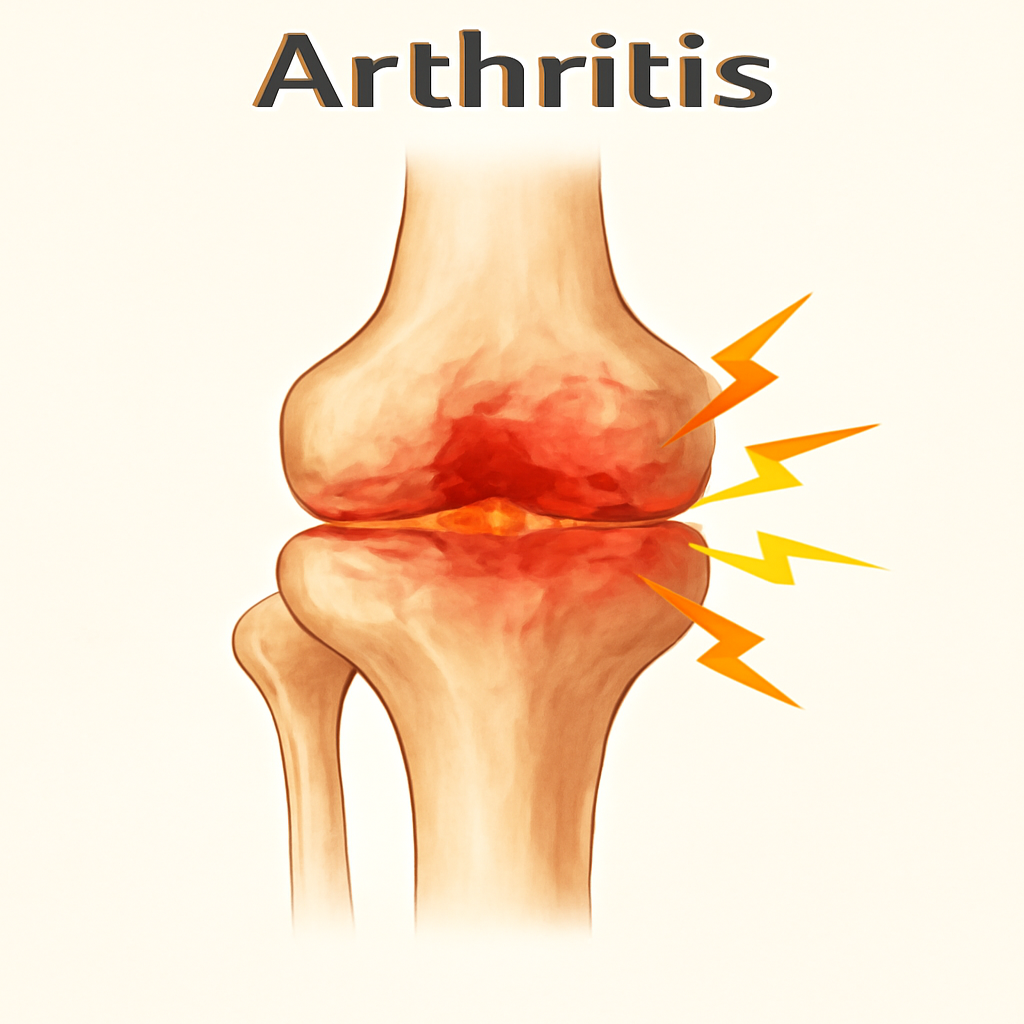

# Bones & Joint